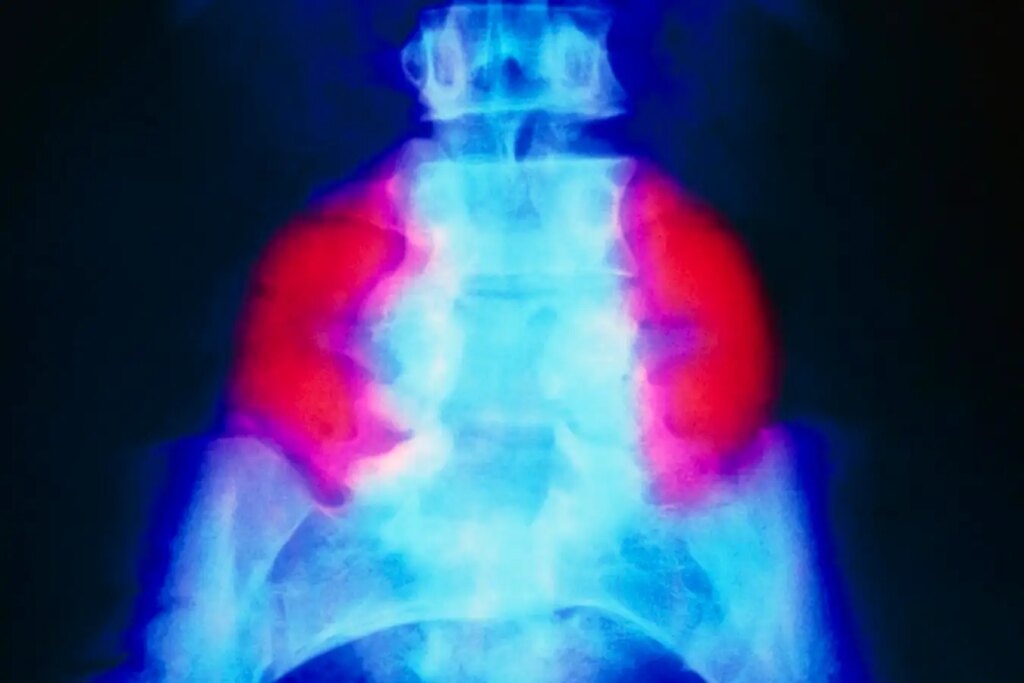

False color radiograph illustrating large neural tube defects (red) on both sides of the lower back in a spina bifida patient

Spina bifida, affecting approximately 1 in 2,800 births annually in the United States, occurs when a baby’s spine and spinal cord do not fully develop in utero. The most severe form, myelomeningocele, involves the spinal cord and surrounding tissues protruding through vertebrae, often leading to mobility challenges and bowel or bladder control issues. The precise cause of spina bifida remains unclear, although a deficiency in folic acid during pregnancy can heighten risks.